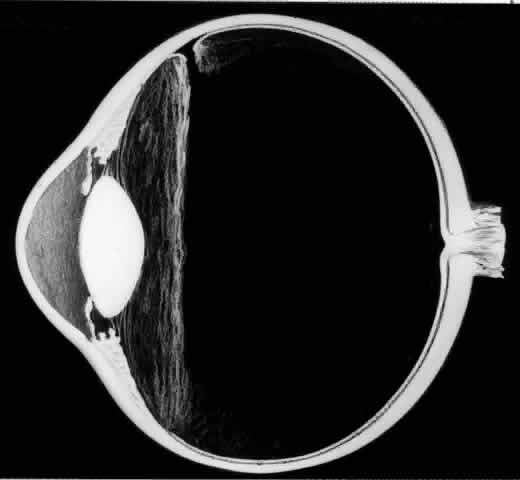

The earliest biomicroscopic changes preceding the development of a giant retinal tear were syneresis and liquefaction of the vitreous gel, converting the posterior and central portions of the vitreous body into a large lacuna (Fig. 14). Later, the anterior gel became condensed, and its posterior aspect formed an equatorially oriented membrane extending across the vitreous cavity (Fig. 15). This membrane did not oscillate with ocular movements, suggesting that it was under tension. Marked contraction of this membrane seems responsible for tearing the retina along the posterior border of the vitreous base (Fig. 16). Liquefied vitreous gel facilitated inversion of the posterior retinal flap (Fig. 17).

Fig. 15. In later biomicroscopic changes preceding a nontraumatic giant retinal break, the anterior vitreous gel becomes condensed and a membrane forms its posterior aspect.

Fig. 16. Contraction of this equatorially oriented membrane extending across the vitreous cavity produces a giant tear along the posterior border of the vitreous base.

Fig. 17. After the formation of a giant retinal tear, the posterior retinal flap inverts into the liquefied vitreous (arrow).